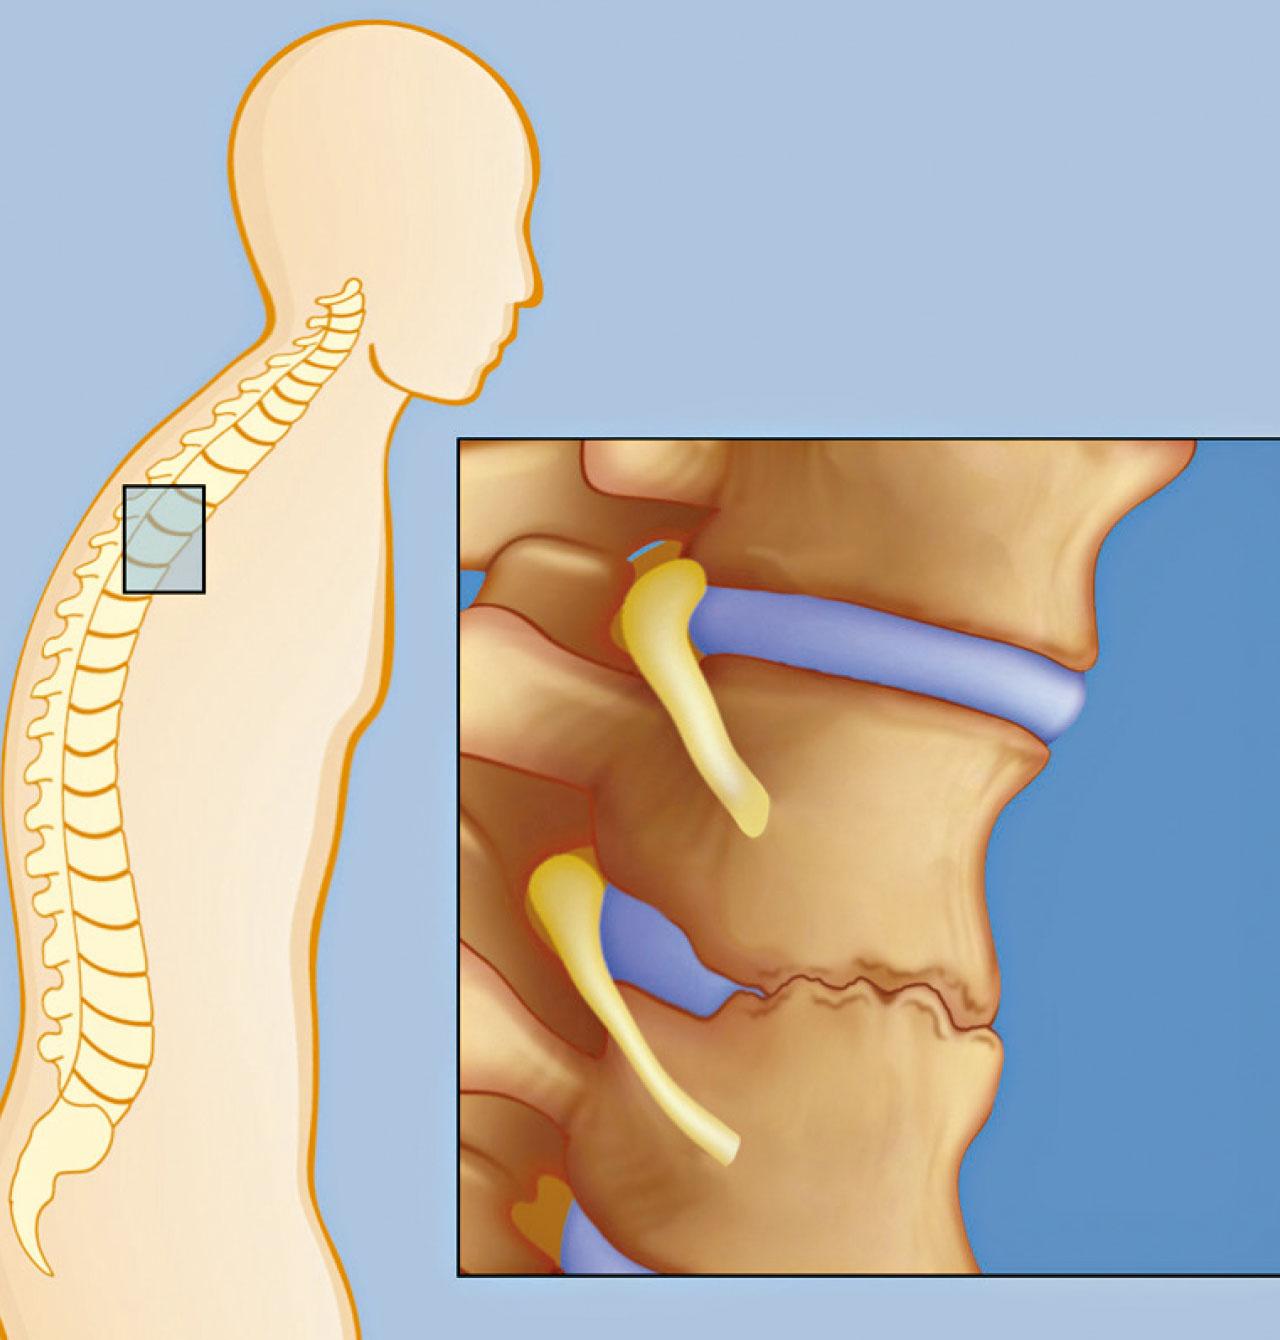

強直性脊椎炎患者起初常見腰背痛問題。

強直性脊椎炎嚴重可使關節融合。

自體免疫疾病大都不易斷尾,以強直性脊椎炎為例,患者的脊椎、髂關節及髖關節等持續性的炎症,令受影響的位置疼痛、僵硬,脊骨鈣化嚴重的話會影響活動能力,亦可能變駝背,如波及肋骨甚至會感呼吸困難。強直性脊椎炎主要影響年輕男性,大部分病友在20至30歲之間首次病發。臨床上,亦有十多歲的年輕人出現類近疾病。強直性脊椎炎的治療上,會用到非類固醇消炎止痛藥、柳氮磺胺嘧啶等,以紓緩痛楚和炎症,但對脊椎炎症效果有限。